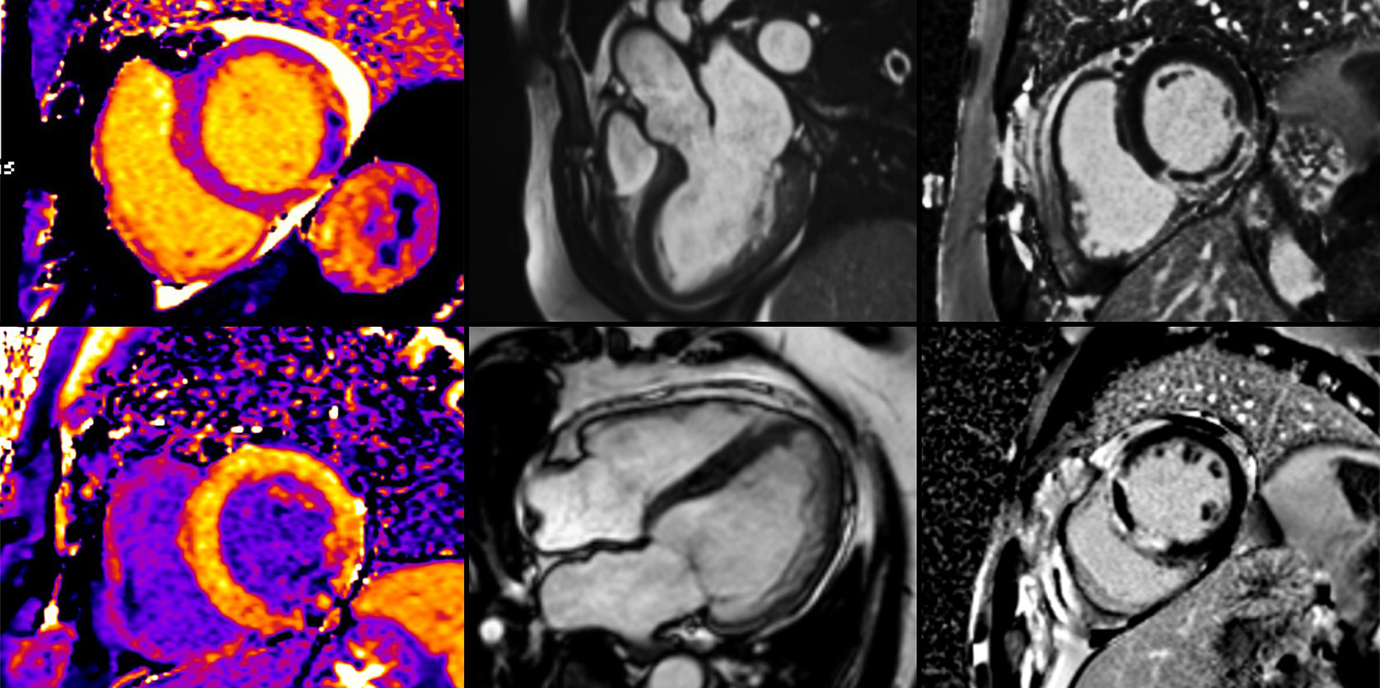

Kardiale MRT liefert umfassendes Bild

„Wir konnten zeigen, dass es besonders während der COVID-19 bedingten Restriktionen zu einer Zunahme der Infarktgröße gekommen ist“, beschreibt Kardiologe Sebastian Reinstadler die zentrale Erkenntnis der Innsbrucker Studie, für die insgesamt 474 Patient:innen einer kardialen MRT wenige Tage nach dem Akutereignis unterzogen wurden. Die kardiale Magnetresonanztomographie (MRT) ist der nicht-invasive Goldstandard für eine umfassende Charakterisierung des Myokardgewebes nach einem STEMI, mit der sich insbesondere die Schwere der Gewebsschädigung, ausgedrückt als Infarktgröße, mikrovaskuläre Obstruktion (MVO) und intramyokardiale Blutung (IMH), sehr genau bestimmen lässt. Sowohl die Größe als auch der Schweregrad des Infarktes, der in der ersten Woche nach einem STEMI mittels kardialer MRT dargestellt werden kann, stehen in sehr engem Zusammenhang mit der funktionellen Erholung des Herzmuskels, einer zukünftigen chronischen Herzinsuffizienz und letztlich auch der kardiovaskulären Mortalität.